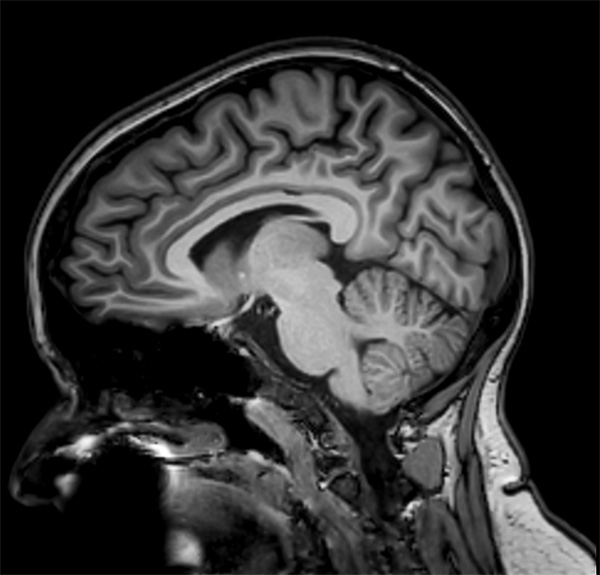

Comprehensive Brain imaging at 3.0T

• Clinical Application